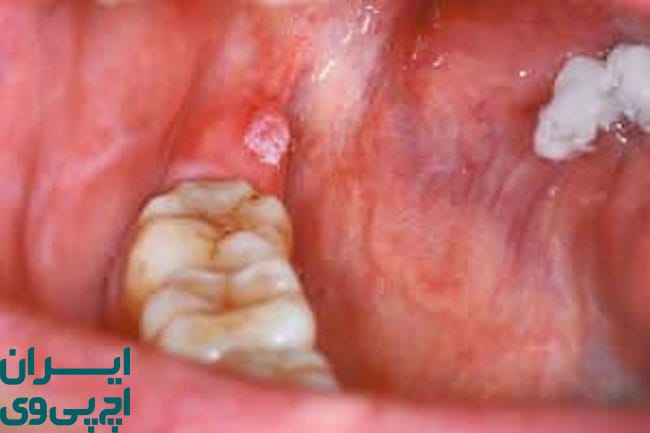

یکی از چالشهای بزرگ در تشخیص HPV دهانی، خاموش بودن علائم آن در مراحل اولیه است. بسیاری از افراد ممکن است برای مدت طولانی ناقل این ویروس باشند بدون آنکه متوجه نشانهای شوند. با این حال، در برخی افراد علائمی مانند زخمهای مزمن در دهان، وجود تودههای کوچک گوشتی، خارش یا درد گلو، یا تغییر صدا ممکن است ظاهر شود. این علائم اغلب با مشکلات ساده دهانی اشتباه گرفته میشوند و به همین دلیل افراد از پیگیری پزشکی غفلت میکنند.

در موارد پیشرفتهتر، HPV دهانی میتواند با رشد غیرعادی بافت در نواحی مانند لوزه، قاعده زبان، یا سقف نرم دهان همراه باشد. این رشدها ممکن است خوشخیم باشند اما در برخی موارد میتوانند سرطانی شوند. انواع پرخطر ویروس HPV، بهویژه نوع ۱۶، بیشتر در بروز سرطانهای مرتبط با حلق و گلو نقش دارند. به همین دلیل، وجود زخمهای ماندگار یا احساس وجود توده در دهان یا گلو باید جدی گرفته شود.